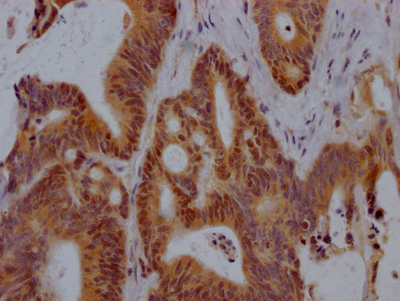

圖片:

應(yīng)用范圍:ELISA, IHC

Application Recommended Dilution IHC 1:20-1:200 -